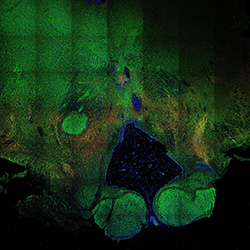

22PCW

DAPI

22PCW human midbrain

GFAP

TH

Merged